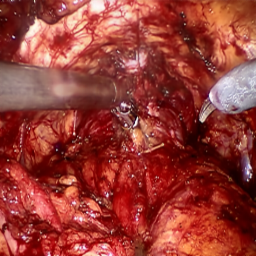

Refer to caption (a) Input Refer to caption (b) case1 Refer to caption (c) case2 Refer to caption (d) case3 Refer to caption (e) Ours Refer to caption (f) Target

Figure 4: Ablation comparisons sampled from the DesmokeData and LSD3K datasets. The first two rows are from DesmokeData and the last two rows are from LSD3K. (settings: case1 = ADA+CrossGating, case2 = DHA+CrossGating, case3 = DHA+ADA).

IV-D Ablation Studies

To validate the effectiveness and individual contributions of the core components of our proposed RGA-Net, we conducted a series of ablation experiments on the DesmokeData dataset. We systematically analyzed the impact of our key designs: the DHA module, the ADA module, and the Cross-Gating (CG) mechanism for feature fusion. In these studies, we created several variants of our network by removing or replacing one component at a time and evaluated their performance. The quantitative results of these experiments are presented in Table II, and qualitative visual comparisons are shown in Fig. 4.

IV-D1 Effectiveness of the Dual-Stream Hybrid Attention Module

The DHA module is designed to capture both local surgical details and global illumination changes by combining shifted window attention with a frequency-domain processing branch. To ablate its effect, we replaced the DHA modules in the encoder with standard Swin Transformer blocks, thus removing the spectral pathway and the hybrid attention mechanism. As demonstrated in Table II, this variant experienced a significant drop in performance. This decline highlights the importance of integrating frequency-domain information, which is crucial for handling the complex light scattering caused by surgical smoke and restoring high-frequency textural details. The results confirm that the dual-stream approach provides a richer feature representation than spatial attention alone.

IV-D2 Effectiveness of the Axis-Decomposed Attention Module

We then investigated the contribution of the ADA module, which is employed in the decoder and latent space to efficiently process multi-scale features. We created a variant where the ADA modules were substituted with a more conventional self-attention mechanism without the block and grid axis decomposition. The results in Table II show a clear degradation in performance for this variant compared to the full model. This outcome validates that factorizing attention along two distinct axes allows the model to capture both fine-grained local patterns and long-range spatial dependencies more effectively and efficiently. The ADA module’s design provides a powerful yet computationally manageable way to model complex feature relationships during the reconstruction phase.

IV-D3 Effectiveness of the Cross-Gating Mechanism

Finally, we analyzed the efficacy of the cross-gating mechanism used for multi-scale feature fusion between the encoder and decoder. We replaced our CG blocks with a standard skip-connection method, specifically simple concatenation followed by a convolutional layer, as is common in many U-Net-based architectures. As shown in Table II, this change resulted in a substantial performance decrease. This finding underscores the superiority of the bidirectional feature modulation offered by our CG mechanism. Unlike simple fusion, cross-gating allows the encoder and decoder pathways to selectively amplify relevant features and suppress irrelevant information from each other, leading to a more refined and effective integration of multi-scale context, which is vital for high-quality image reconstruction.

In conclusion, the ablation studies comprehensively demonstrate that each of our proposed components—DHA, ADA, and CG—is integral to the overall performance of RGA-Net. The full model consistently outperforms all ablated variants, proving the synergistic benefits of our architectural design for the challenging task of surgical smoke removal.